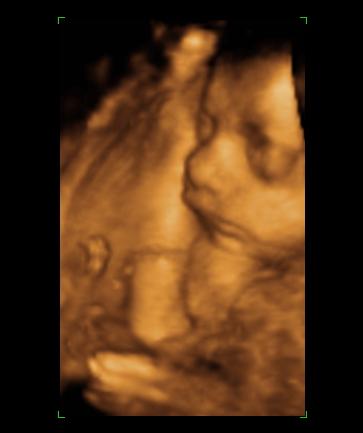

A doki szerint pufók kislány

És egy tappancs 2008.03.08 19:45